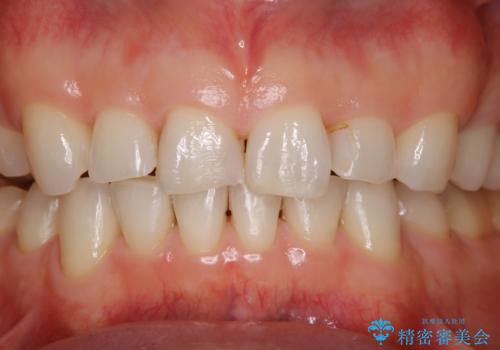

前歯のステイン(着色)をPMTCでキレイに

- コーヒーを普段からよく飲むため、着色・ステインが気になるとのことで来院されました。着色が前歯のみに付着していたためPMTC自費クリーニングの30分コースを行いました。